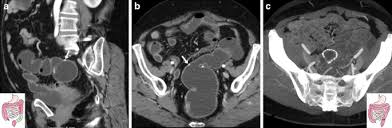

Reviewing The Management Of Obstructive Left Colon Cancer Assessing The Feasibility Of The One Stage Resection And Anastomosis After Intraoperative Colonic Irrigation Clinical Colorectal Cancer

Reviewing The Management Of Obstructive Left Colon Cancer Assessing The Feasibility Of The One Stage Resection And Anastomosis After Intraoperative Colonic Irrigation Clinical Colorectal Cancer from els-jbs-prod-cdn.jbs.elsevierhealth.com